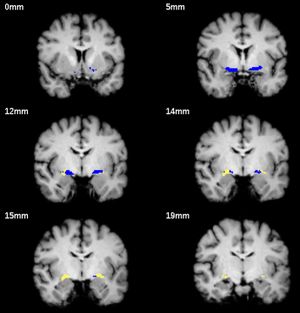

Publication: Brain Behav. 2015 Dec 29;6(1):e00421. PMID: 27110442 | PDF Authors: Lammers F, Mobascher A, Musso F, Shah NJ, Warbrick T, Zaborszky L, Winterer G. Institution: Department of Anaesthesiology and Surgical Intensive Care Medicine Charité, University Medicine Berlin, Berlin, Germany. Background/Purpose: Cortical acetylcholine released from cells in the basal forebrain facilitates cue detection and improves attentional performance. Cholinergic fibres to the cortex originate from the CH4 cell group, sometimes referred to as the Nucleus basalis of Meynert and the Nucleus subputaminalis of Ayala. The aim of this work was to investigate the effects of volumes of cholinergic nuclei on attention and executive function. Methods: The volumes of CH4 and CH4p subregions were measured in a subgroup of 38 subjects (33.5 ± 11 years, 20 females) from a population-based cohort study of smokers and never-smokers who have undergone additional MR imaging. To define regions of interest, we applied a DARTEL-based procedure implemented in SPM8 and a validated probabilistic map of the basal forebrain. Attention and executive function were measured with Trail-Making Test (TMT A+B) and Stroop-Task. Results: We found a quadratic effect of the left CH4 subregion on performance of the TMT. Extremely small as well as extremely large volumes are associated with poor test performance. Conclusions: Our results indicate that a small CH4 volume predisposes for a hypocholinergic state, whereas an extremely large volume predisposes for a hypercholinergic state. Both extremes have detrimental effects on attention. Comparable nonlinear effects have already been reported in pharmacological studies on the effects cholinergic agonists on attention. |

Segmentation example for one brain. The blue ROI refers to CH4, CH4p is shown in yellow. Slices were chosen with the intention to show that CH4p covers a cell cluster often referred to as the Nucleus subputaminalis of Ayala which is rostrolateral extension of the NBM (at 12, 14 and 15 mm). Slice positions are indicated with reference to the most anterior slice on the top left. 3D Slicer 4.3.0 was used to calculate the volume of each labelled region in the map. |